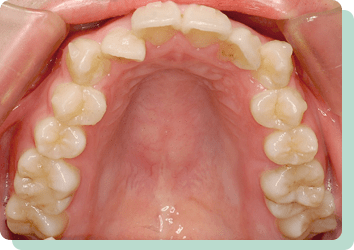

CASES